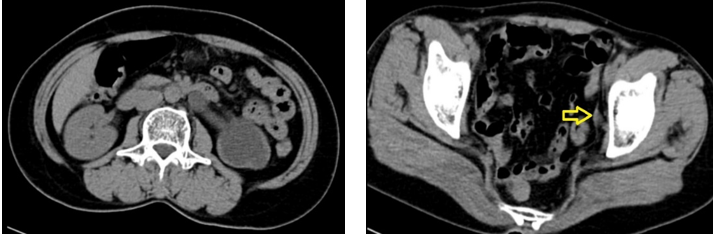

Vừa qua khoa Ngoại tổng hợp, Bệnh viện Đa khoa tỉnh Quảng Trị đã thực hiện thành công phẫu thuật nội soi ổ bụng cắm lại niệu quản cho một bệnh nhân nữ 55 tuổi. bệnh nhân này có tiền sử nội khoa bình thường, 3 năm trước được phẫu thuật cắt tử cung toàn phần đường bụng. gần đây thấy đau tức vùng hông trái, đi siêu âm phát hiện thận trái ứ nước độ 4 nên nhập viện. Thăm khám lúc vào viện thấy bệnh nhân đau tức vùng hông trái, thận trái không lớn , siêu âm thấy thận trái ứ nước độ 4 nhu mô thận mỏng, không thấy thấy sỏi cản quang niệu quản. Trên phim chụp hệ niệu không chuẩn bị không phát hiện sỏi cản quang hệ tiết niệu. Bệnh nhân sau đó được chụp niệu đồ tĩnh mạch thấy chức năng thận trái giảm mạnh. Do chưa tìm thấy nguyên nhân ứ nước, bệnh nhân được chỉ định chụp cắt lớp vi tính không thuốc (CT Scan), trên hình ảnh thấy thận trái không lớn, ứ nước độ IV, nhu mô thận mỏng, niệu quản giãn 9-10mm từ đoạn bụng đến đoạn chậu, rất hẹp ở đoạn tiểu khung, chẩn đoán cuối cùng là thận trái ứ nước độ IV do hẹp niệu quản đoạn tiểu khung.

Hình 1 : Thận trái ứ nước độ 4 và vị trí niệu quản hẹp (mũi tên vàng)

Bệnh nhân được chỉ định nội soi nong niệu quản hẹp nhưng thất bại do niệu quản hẹp khít tại vị trí cách lỗ niệu quản khoảng 4cm.Sau đó Bệnh nhân được chỉ định mổ nội soi ổ bụng cắm lại niệu quản theo phương pháp Lich – Grégoir. Phẫu thuật được thực hiện với 3 trocar (1 trocar 10mm ở rốn và 2 trocar 5mm ở 2 hố chậu) . Chỗ hẹp tại vị trí gần sát bàng quang do xơ dính của lần phẫu thuật trước.